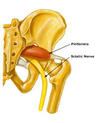

Músculo piriforme - Conceitos gerais

- Origem: Superfície pélvica do sacro e margem da incisura isquiática maior

- Inserção : Trocânter Maior

- Inervação: Nervo para o músculo piriforme (S2)

- Ação: Abdução e Rotação Lateral (externa) da Coxa